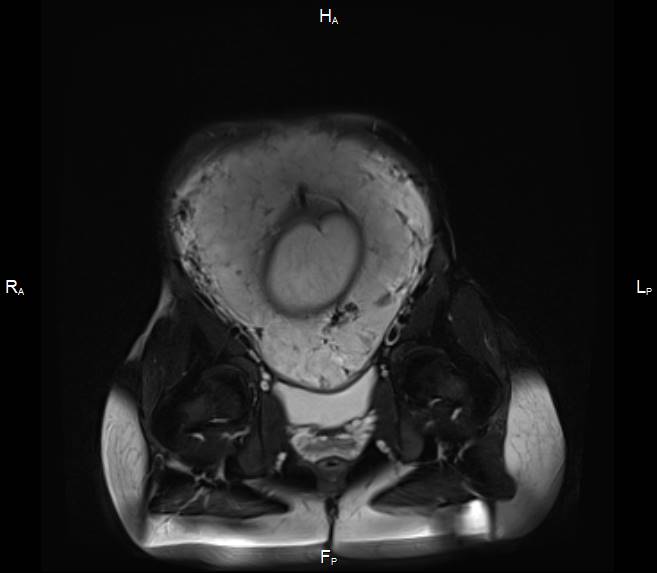

Первичный, или «материнский» этап, длительностью 3–5 минут, при котором получаемые Т2-ВИ многоплоскостные ортогональные МР-изображения (рисунок 1) ориентируются согласно анатомии беременной; целью его является оценка сегментарного расположения плацентарного диска в полости матки, контуров и размеров матки.

|

|

|

| А | Б | В |

| Рисунок 1 – Беременность 36 нед. МРТ плаценты. Первичный, «материнский» этап исследования. Т2 ВИ в сагиттальной (а), корональной (б) и аксиальной (в) плоскостях | ||

Завершающий, или «тазовый» этап, длительностью не более 5–10 мин, при котором прицельно оценивается нижние сегменты матки, внутренний зев, шейка матки, мочевой пузырь, смежные ткани и органы таза беременной с целью выявления критериев прорастания плаценты, которые могут соответствовать 3 (a, b, c) степени согласно классификации FIGO (2018) для клинической диагностики группы плацентарных нарушений адгезивно-инвазивного спектра (рисунок 2).

|

||

| а. | ||

|

|

|

| б. | в. | г. |

| Рисунок 2 – Беременность 36 нед. МРТ плаценты. Основной, «плацентарный» этап исследования. Варианты позиционирования срезов для получения ортогональных изображений плаценты в косо-сагиттальной (б), косо-корональной (в) и косо-аксиальной (г) плоскостях относительно анатомии беременной по МР-изображениям первичного этапа (а) | ||